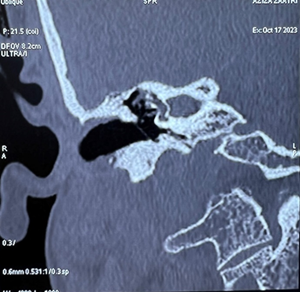

On the ct scan of the temporal bone, the right

ear cavity had a soft tissue density, incomplete filling of the epitympanum and

mesotympanum, by well-defined, encapsulated tissue formations, one of which is

pedicled opposite the jacobson's nerve, thining of the tegmen tympani,

ossicular lysis, fistula between the upper semicircular canal and the tympanic

cavity and mastoid cell filling (figure

4).

Figure 4: ct scan of the temporal bone in coronal and axial cuts: showing soft tissue density within the right middle ear cavity, pedicle tissue formation opposite the jacobson nerve, ossicular lysis, fistula between the upper semicircular canal and the tympanic cavity.